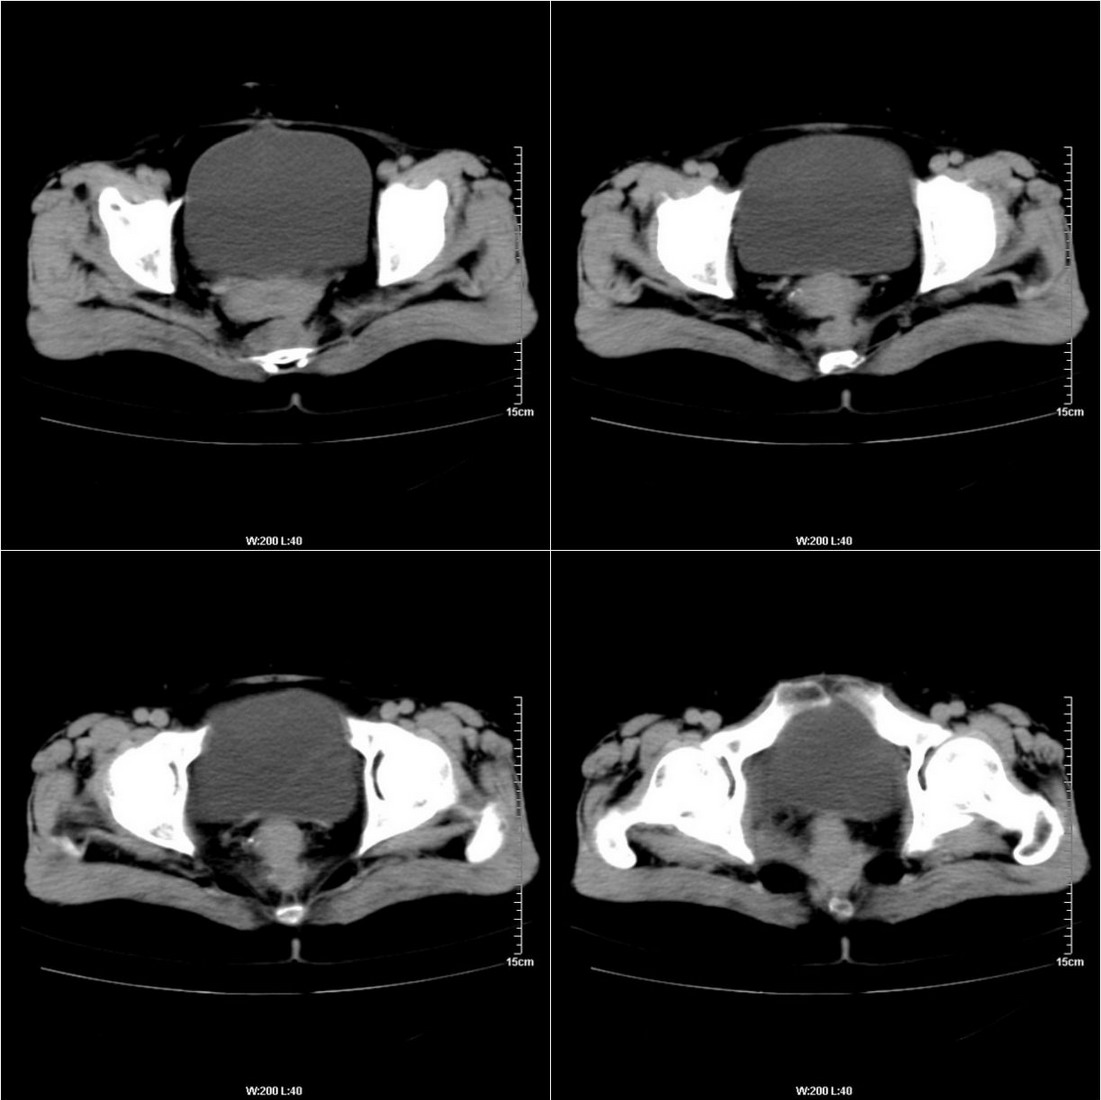

不知道病人的直肠癌手术方式如何,直肠已经全部切除,乙状结肠造瘘于左下腹,肛门应该也没有保留吧?如此,应该是复发了:

病变于肛尾韧带、右侧坐骨肛门窝内并顺右侧肛提肌向右侧闭孔内肌蔓延,骶前软组织内也形成了肿块,麻烦啊!

典型直肠癌术后骶骨前转移复发.

考虑直肠癌术后复发并侵犯周围组织。

考虑直肠癌术后复发并侵犯周围组织